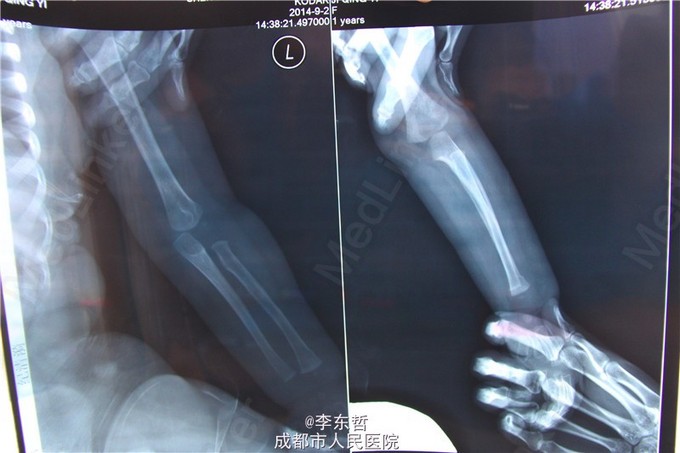

小儿左桡骨远端青枝骨折

患儿1岁, 在练习走路过程中不慎摔倒, 左手撑地. 回家发现爬行困难, 左手不敢着地. 来院拍X光后, 确定为左桡骨青枝骨折.